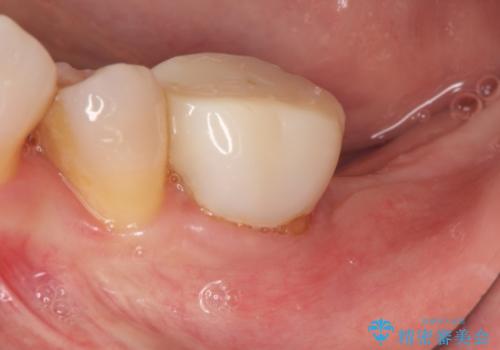

[歯の破折] インプラント埋入を行うための大規模骨造成